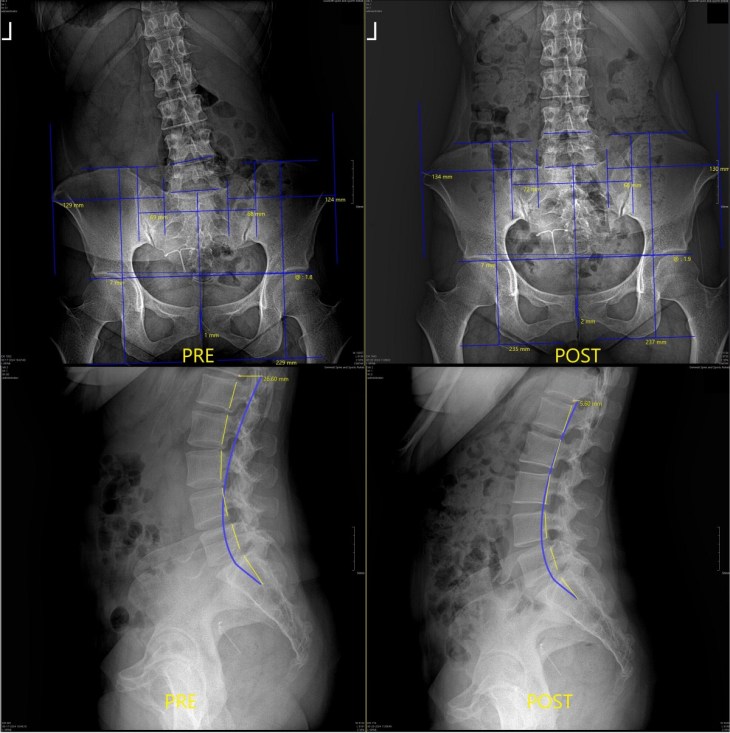

◇ 첨단 장비와 가족 중심 치료

스와니로 확장 이전한 병원은 최신 교정 장비와 운동 재활시설을 갖췄다. 환자 개개인의 상태에 맞춰 레이저치료·견인치료·운동 재활치료를 진행하고, 환자 개개인에 특화해 사용할 수 있는 특수 교정기를 이용해 척추 곡선과 측만증 치료에 사용하고 있다.

척추교정 이전(왼쪽)과 이후 비교 X레이 사진